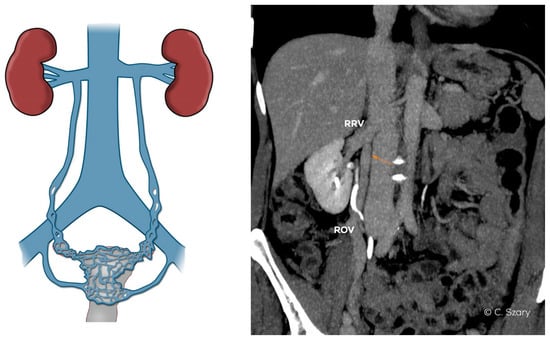

- atypical drainage of the right ovarian vein into the trunk of the right renal vein (Figure 7).

| - absence or hypoplasia of RRV |

| - atypical ROV drainage (draining into the main branch of the RRV or accessory RRV) |

| - high localized ostium of ROV to IVC (on its ventral side) |

| - distended ostium of the ROV typically draining into the IVC |

| - lack of an ostial or subostial valve in the ROV trunk |

| - combined anatomy of the ROV system (e.g., duplication of the ROV trunk) |